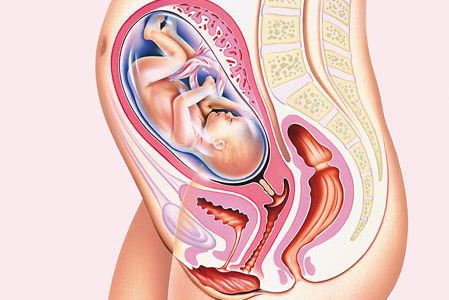

Guida gravidanza: settimo mese

Per la rubrica Guida gravidanza oggi vedremo il settimo mese di gravidanza è quello che va da 26+3 a 30+4 settimane: con il settimo mese inizia anche l’ultimo trimestre di gravidanza.

SETTIMO MESE: COSA FARE

Se non avete ancora fatto acquisti per il piccolo questo è il momento giusto; è importante sia per la mamma che per la coppia restare calmi. Immagino che se siete alla prima gravidanza potrebbe essere difficile: ricordatevi sempre che per tutti i nove mesi (e anche dopo) potete sempre rivolgervi al ginecologo, ad un’ostetrica anche per dei piccoli dubbi.